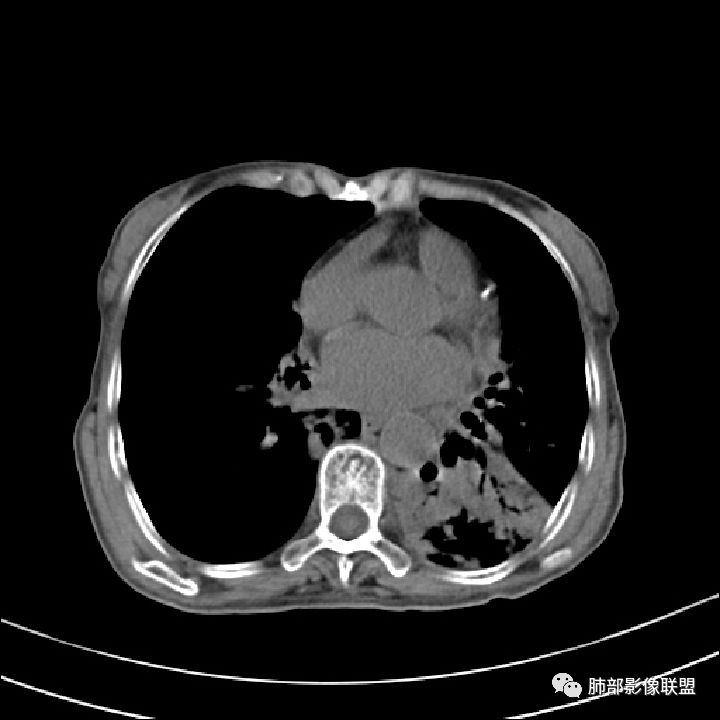

这些应该是胸水

支气管扩张、扭曲成团,附近钙化灶

纵膈也左移了

这例左下叶的体积是整体缩小的,左下叶的支气管主干稍微小一点点,然后左上叶的下舌段也有类似的病灶,然后我们看到一团乱的支气管扩张,但它有特点,边缘凹凸不平。那什么样的支气管扩张边缘会如此凹凸不平呢,等我截个图:

看最后一幅图,上面这个支气管,有可能是淋巴瘤,为什么?他的支气管稍扩张,直达远端、实变。

首先这幅图支气管很多地方是扭曲的,远端扩张的特别厉害。如果是肿瘤,首先考虑淋巴瘤,因为支气管可直达远端,稍扩张,但是它的前提是周围要实性占位的,而且它不会这样扭曲变形。我们看这个病例的支气管扩张,它支气管扩张占大部分区域,中间稍有些实性的结构,这就不符合了。这幅图你会发现所有支气管都是扩张的,实性部分偏少,外围胸水。所以我更倾向慢性炎性病变,能够引起支气管扩张的炎性病变有哪些?结核?NTM?支扩伴感染?大方向是慢性炎性病变。这些左下肺播散出来的病灶,咳中等量黄浓痰,我考虑还可能合并细菌感染。